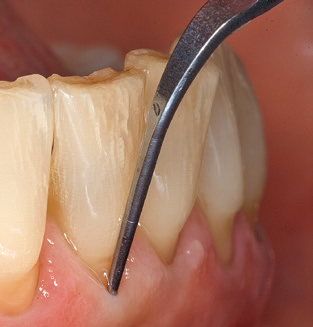

Die gute Ausleuchtung des Arbeitsfeldes stellt eine wesentliche Erleichterung dar. Bei dem von den Autoren genutzten System ist dies gelungen, indem ein 5facher LEDRing in das Handstück integriert wurde. Natürlich werden für dieses System unterschiedliche Arbeitsspitzen für die jeweiligen Indikationsbereiche angeboten. Eine gerade, universell einsetzbare Spitze ist das Basisinstrument zur maschinellen Instrumentierung natürlicher Zähne (Abb. 5a und b). Für schwer zugängliche Bereiche im Seitenzahnbereich werden gebogene Spitzen angeboten, die auch einen Zugang zu freiliegenden Furkationen ermöglichen (Abb. 6).

Nach der maschinellen Reinigung der Zahn und Implantatoberflächen erfolgt eine manuelle Instrumentierung der natürlichen Zahnoberflächen mit konventionellen Handinstrumenten. Bei der manuellen Reinigung ist insbesondere auf einen korrekten Anstellwinkel, eine ausreichende Schärfe, eine gute Abstützung und auf eine von apikal nach koronal gerichtete Arbeitsweise der Kürette zu achten. Zur Nachinstrumentierung der Implantatkonstruktionen sollten entweder Titan oder Carbonküretten verwendet werden (Abb. 8). Ergänzend zum Einsatz von Ultraschallgeräten können in der Erhaltungstherapie auch Pulverstrahlgeräte genutzt werden. Dabei ist jedoch zu berücksichtigen, dass diese Verfahren nicht zum Entfernen harter Beläge geeignet sind und daher die Verwendung von Hand oder Ultraschallinstrumenten nicht komplett ersetzen können. Abschließend erfolgt in jedem Fall eine mechanische Politur der zugänglichen Zahn und Implantatoberflächen mit Polierkelchen und Polierpasten (Abb. 9).